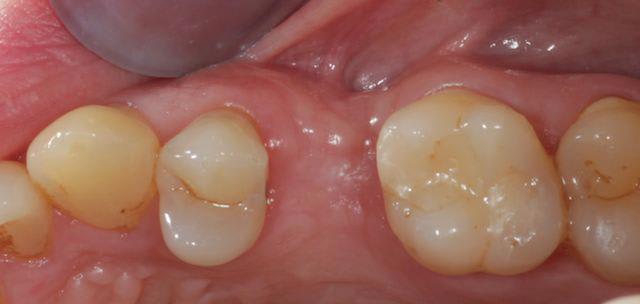

tiens pour faire avancer le débat un cas de ROG verticale et horizontale, avec membrane PTFE armé titane.

486849 10151469282438909 1569932967 n wfvtaw - Eugenol

67354 10151469282783909 1467702450 n qvjnob - Eugenol

563553 10151469282653909 1593165568 n dihjew - Eugenol

1853 10151469282613909 1015929230 n hhsfft - Eugenol

555374 10151469088933909 1265673870 n ui2jmo - Eugenol

72650 10151469088903909 1954739928 n ygymol - Eugenol

450 10151469088763909 748076808 n aldyeu - Eugenol

421967 10151469088718909 212073595 n t3r6tw - Eugenol